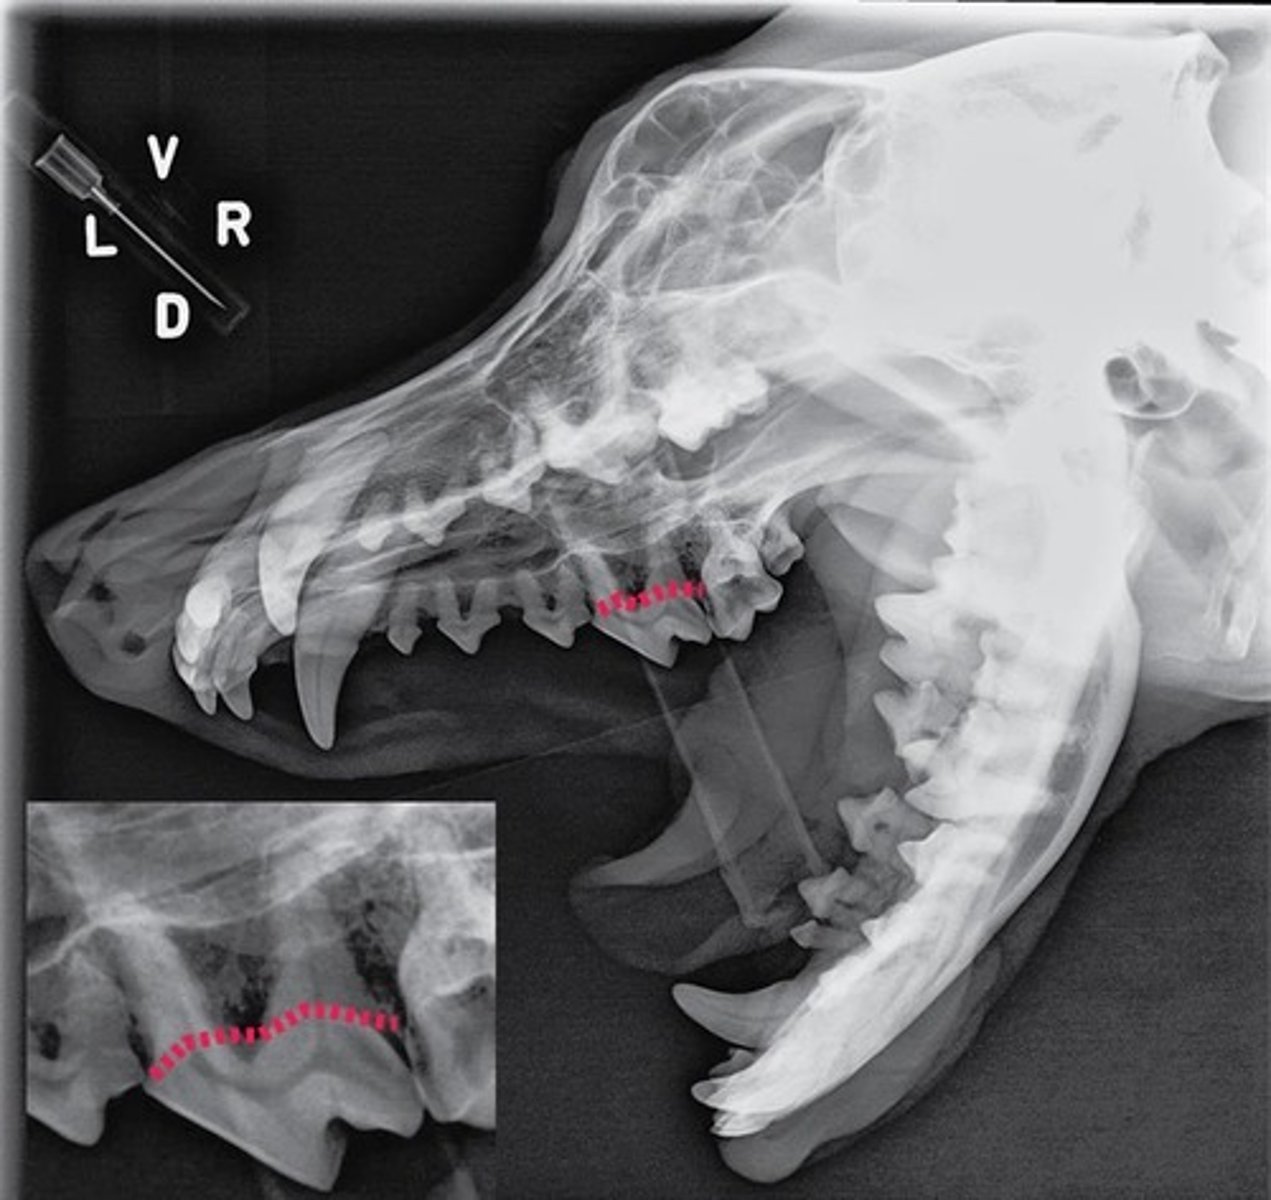

Identify the type of tooth indicated by the arrow.

Molar

Identify the type of tooth indicated by the arrow.

vestibular, buccal, facial surface

Identify the tooth surface the red line being pointed to by an arrow represents

lingual surface

Identify the tooth surface the red line being pointed to by an arrow represents

mesial surface

On the first molar, identify the surface the red line being pointed to by an arrow represents.

distal surface

On the first molar, identify the surface the red line being pointed to by an arrow represents